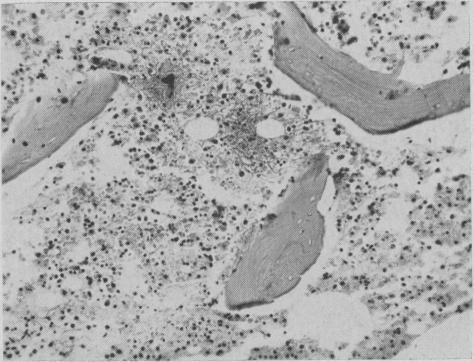

Vincaleukoblastine in the treatment of malignant disease.

Can Med Assoc J. 1961 Sep 2;85(10):584-91.